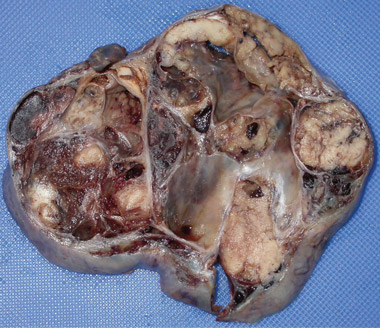

At 59 years of age, a laparotomy was performed and the patient was found to have a large left adnexal mass (Box 1, A) and a normally formed uterus. The mass was removed and a subtotal hysterectomy performed as there was no distinct lower margin of the cervix (Box 1, B). The patient was informed of the operative findings and the diagnosis of intersex. Peripheral blood karyotyping showed a 46,XY genotype. The histopathology of the gonadal tumour showed a sex cord-stromal tumour of indeterminate differentiation (Box 2). The histopathology of the uterus showed simple endometrial hyperplasia. The patient was treated with postoperative chemotherapy, but died 18 months later.

The risk of malignancy in dysgenetic gonads is significantly increased in some patients with DSD.8 The presence of the SPY gene on the GBY region of the Y chromosome is a prerequisite for malignant transformation.9 Tumours can arise in any of the gonadal cells or their precursors.8 Precursor lesions for the development of cancers occur as carcinoma-in-situ in testicular tissue and gonadoblastoma in undifferentiated gonadal tissue. A number of malignant tumour types may occur in dysgenetic gonads.8,10 These include germ cell tumours and sex cord-stromal tumours. Patients presenting with abdominal tumours in dysgenetic gonads in adulthood provide histopathologists with complex diagnostic dilemmas. Histopathological examination of the tumour in our case showed mixed elements, with cells resembling ovarian follicles, testicular tunica, granulosa cells, Sertoli cells and Leydig cells. No germ cell components were identified. The final consensus was a diagnosis of malignant sex cord-stromal tumour of indeterminate differentiation.

It is likely that the oestrogen-secreting gonadal tumour had been present for some years in our patient, resulting in endometrial hyperplasia. The uterus is likely to have been connected to the urethra, with endometrial bleeding causing the apparent haematuria. Persisting elevated levels of oestrogen would also have caused gynaecomastia, which resolved after surgical removal of the tumour. Serum follicle-stimulating hormone was likely to have been suppressed by the elevated level of oestradiol, and a normal level of serum luteinising hormone and low level of testosterone are consistent with the history of incomplete external genital development and infertility.